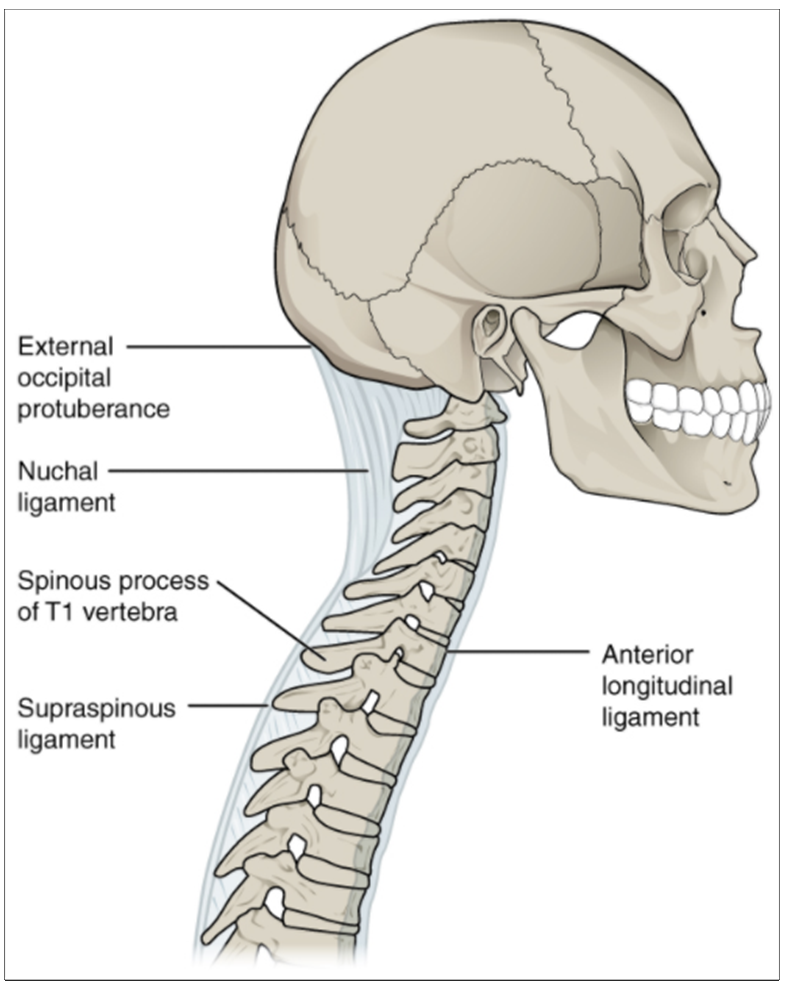

Do You Have Neck Pain? It Could Be Coming From Your Ligaments - Old Post Physical Therapy

Afraid to stick your neck out when it comes to naming cervical spine ligaments? Know the anterior longitudinal ligament (ALL) \u0026 that's ALL? Is the nuchal ligament a NEW CALL for you?

The vertebral column usually contains three curves. The cervical and lumbar curves are convex anteriorly, and the thoracic curve is convex posteriorly. These curves, together with gravity, barricity of the local anesthetic,